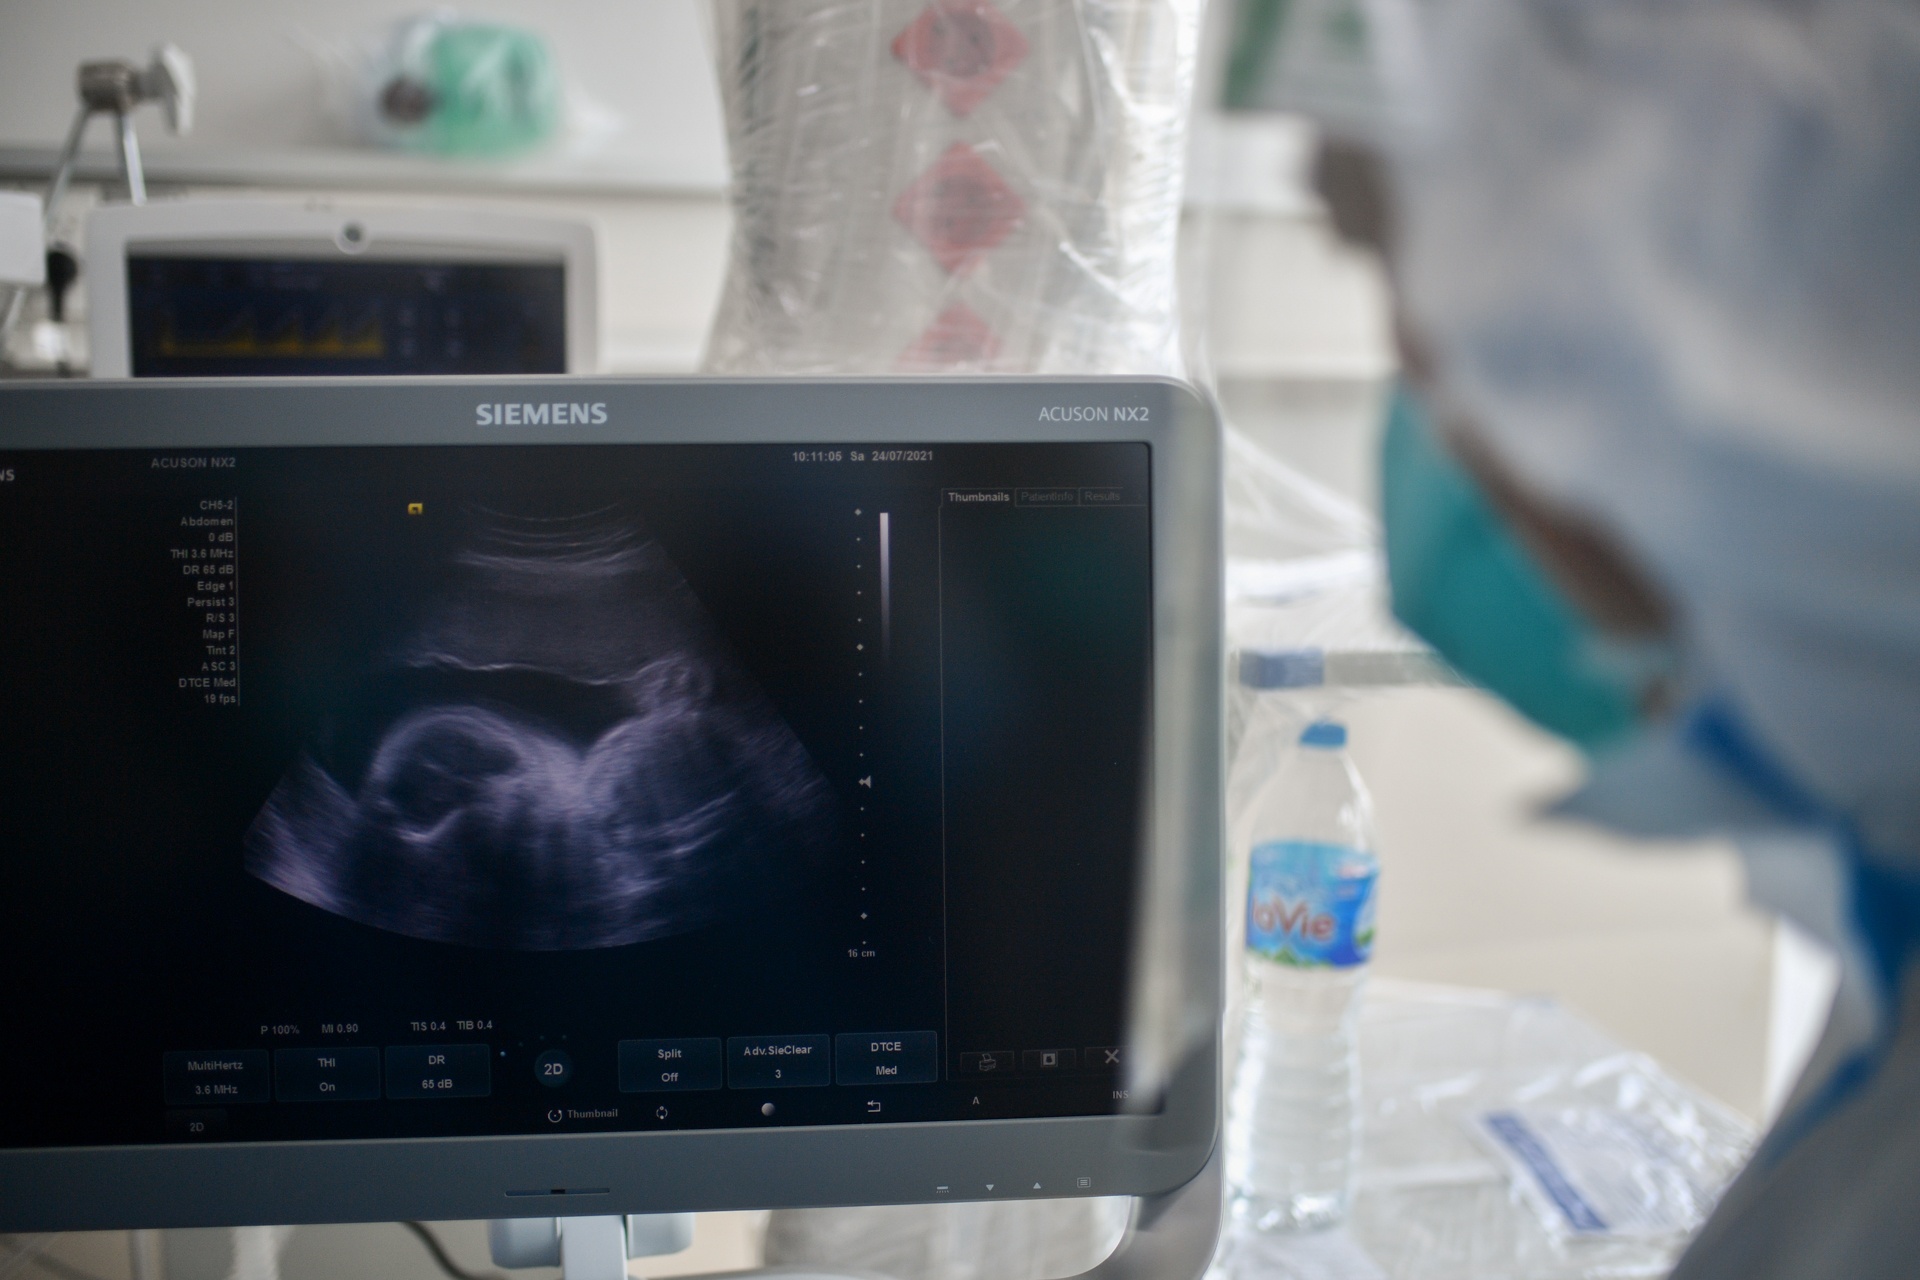

Đều đặn mỗi buổi sáng, anh đến khám, cho thuốc và siêu âm thai nhi. "Chúng tôi đặt mục tiêu phải đảm bảo sự an toàn cho cả 3 mẹ con", nam bác sĩ chia sẻ.

| Bác sĩ Trần Thanh Linh và bác sĩ Trần Hữu Chinh siêu âm và theo dõi tình trạng thai nhi của chị T. |